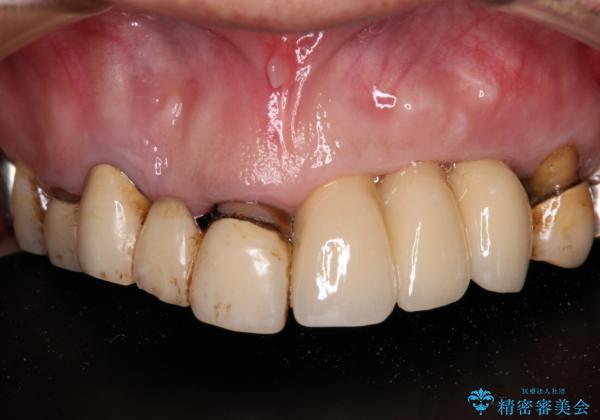

転倒で折れてしまった前歯 インプラントによるオールセラミックブリッジ治療

- 転倒により前歯3本が折れてしまったとのことで、インプラントによる治療を希望して来院された患者様です。

既に近医で真ん中の歯1本は抜歯されており、その隣の2本も破折していると言われたとのことでした。

診断をした結果、前医の診断の通り、2本とも破折しており、既に抜去している歯を含めて3本の抜歯が必要な状態でした。

抜歯する歯の両隣も治療が必要と思える歯であったため、広範囲なオールセラミックブリッジによる治療も提案しましたが、患者様本人の希望もあってインプラント2本による欠損部のみのブリッジ治療を行うこととしました。